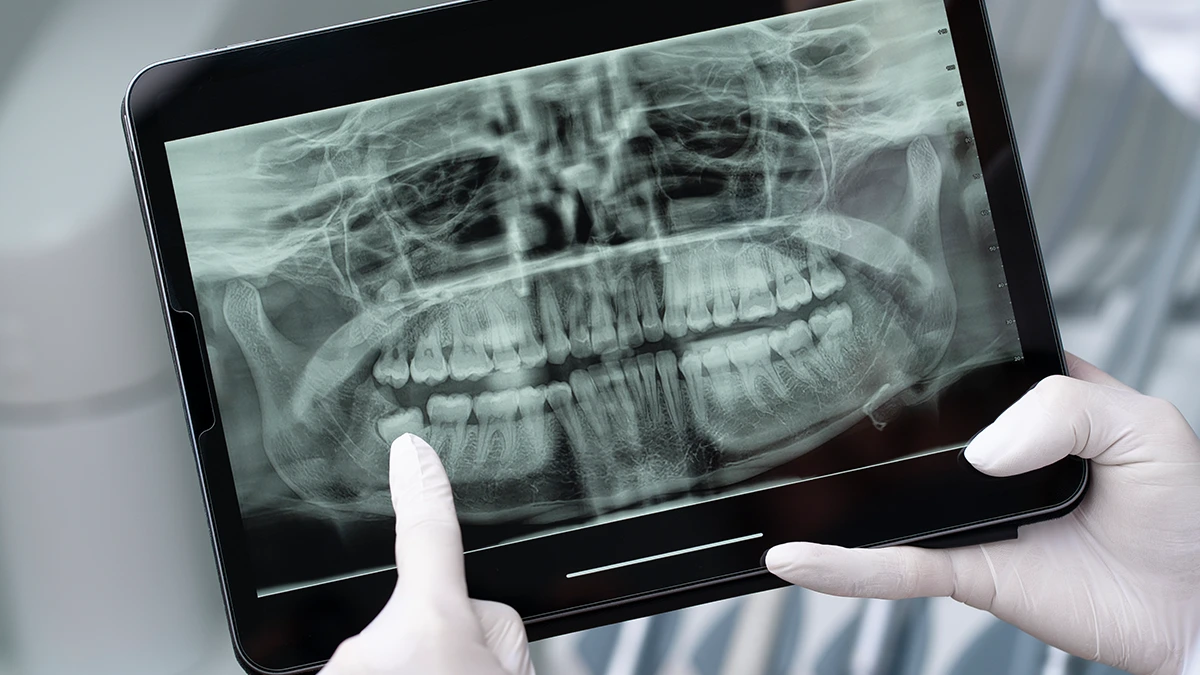

Biliyoruz ki, elinize bir 20’lik diş röntgeni geçtiğinde, o siyah, beyaz ve gri tonlardan oluşan görüntünün ne anlama geldiğini merak edebiliriz. Aslında, diş röntgeni nasıl okunur sorusunun cevabı, deneyimli bir göz için bir hikaye kitabını okumak gibidir. İşte hekimlerimizin bu görüntülerde dikkat ettiği kritik noktalar:

20’lik diş röntgeni, sadece acil bir çekim kararı verileceği zaman değil, aynı zamanda düzenli takip amacıyla da kullanılan vazgeçilmez bir tanı aracıdır. Eğer yirmi yaş dişlerimiz henüz sorun yaratmıyorsa ancak hekimimiz bunların gömülü olduğunu veya potansiyel risk taşıdığını tespit ettiyse, genellikle 6 ayda bir veya yılda bir kontrol röntgenleri çekilmesini tavsiye ederiz. Bu takibin amacı, dişlerin çene kemiği içindeki hareketini, öndeki dişlere yaptığı baskıyı veya kök gelişimindeki ani değişiklikleri izlemektir.

Bu takip süreci, özellikle henüz yirmilik diş kaç yaşında çıkar sorusunun cevabını tam olarak almamış, yani dişin sürmesi beklenen genç hastalarımız için kritiktir. Periyodik diş röntgeni sayesinde, dişteki en ufak bir ilerlemeyi, bir kist oluşumu başlangıcını veya komşu dişte çürük gelişimini bile erken aşamada yakalayabiliriz. Bu sayede, zamanında müdahale ederek olası büyük cerrahi operasyonlardan veya daha komplike tedavilerden kaçınma şansımız olur. Röntgenler sırasında maruz kaldığımız radyasyon dozu, modern dijital cihazlarla oldukça düşüktür; bu nedenle, tanısal faydası, potansiyel risklerinden çok daha fazladır. Biz bu görüntüleri, sizin uzun vadeli ağız sağlığınızın garantisi olarak görürüz.